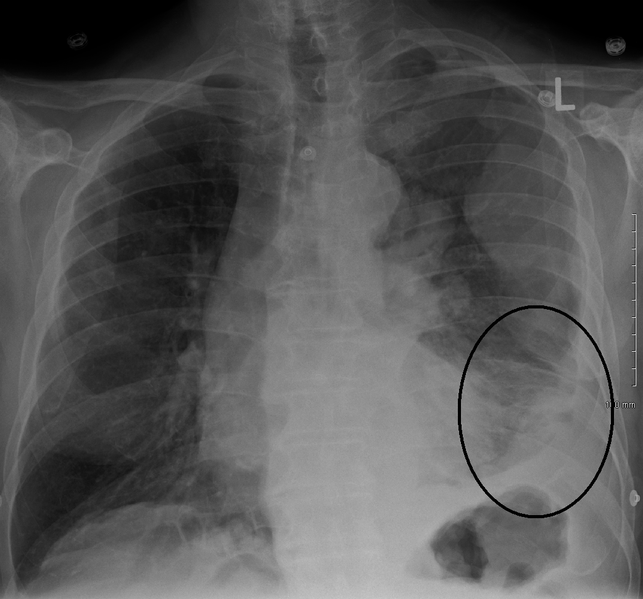

Pleural effusion treatment healthcommunities. Treatment options for pleural effusion are explained including special considerations for empyema and malignant effusion. Management of malignant pleural effusions (ats journals). Imaging techniques. Most patients presenting with malignant pleural effusions have some degree of dyspnea on exertion and their chest radiographs show moderate to. Malignant mesotheliomapatient version national cancer. Information about malignant mesothelioma treatment, causes, clinical trials, and other topics from the national cancer institute. Mesothelioma wikipedia, the free encyclopedia. Find and connect with a top. Mesothelioma you don't have to sue anyone.. Connect with us and get the best information on mesothelioma cancer. Pleural mesothelioma treatment, prognosis &. Get all the answers you need from. What is mesothelioma? Maacenter. Mesothelioma guide treatment options and resources. Epidemiology of malignant pleural mesothelioma uptodate. Mesothelioma is an insidious neoplasm arising from the mesothelial surfaces of the pleural and peritoneal cavities, the tunica vaginalis, or the pericardium. Eighty.

Pleural effusions slideshare. · pleural effusions canmao xie dept. Of pulmonary & critical care medicine 1 st affiliated hospital of sunyat sen university dr. Canmao xie. Mesothelioma malignant get free mesothelioma resources.. Get a free mesothelioma packet with. Malignant pleural mesothelioma an epidemiological. Malignant mesothelioma is a tumour arising from the mesothelial lining of the pleura, peritoneum, pericardium and tunica vaginalis. Pleural mesothelioma is the most. Mesothelioma read about symptoms, treatment and. Get the facts on mesothelioma types (pleural, peritoneal, pericardial), causes (asbestos), cancer diagnosis, prognosis, staging, life expectancy, and treatment. Malignant mesothelioma treatment, prognosis & diagnosis. · malignant pleural mesothelioma. Malignant pleural mesothelioma is the most common type of mesothelioma and occurs in the mesothelial membrane.